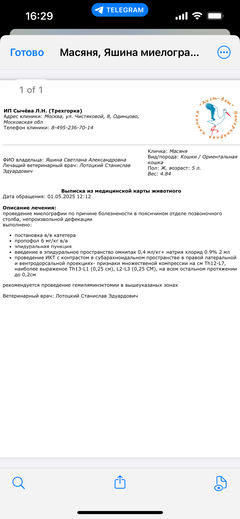

Ярко выраженная болезненность в области крестца, на обезболе полегче. По результатам приема невролога проведена миелография - множественная компрессия, возможно опухоль, возможно грыжа, нужно удалять...